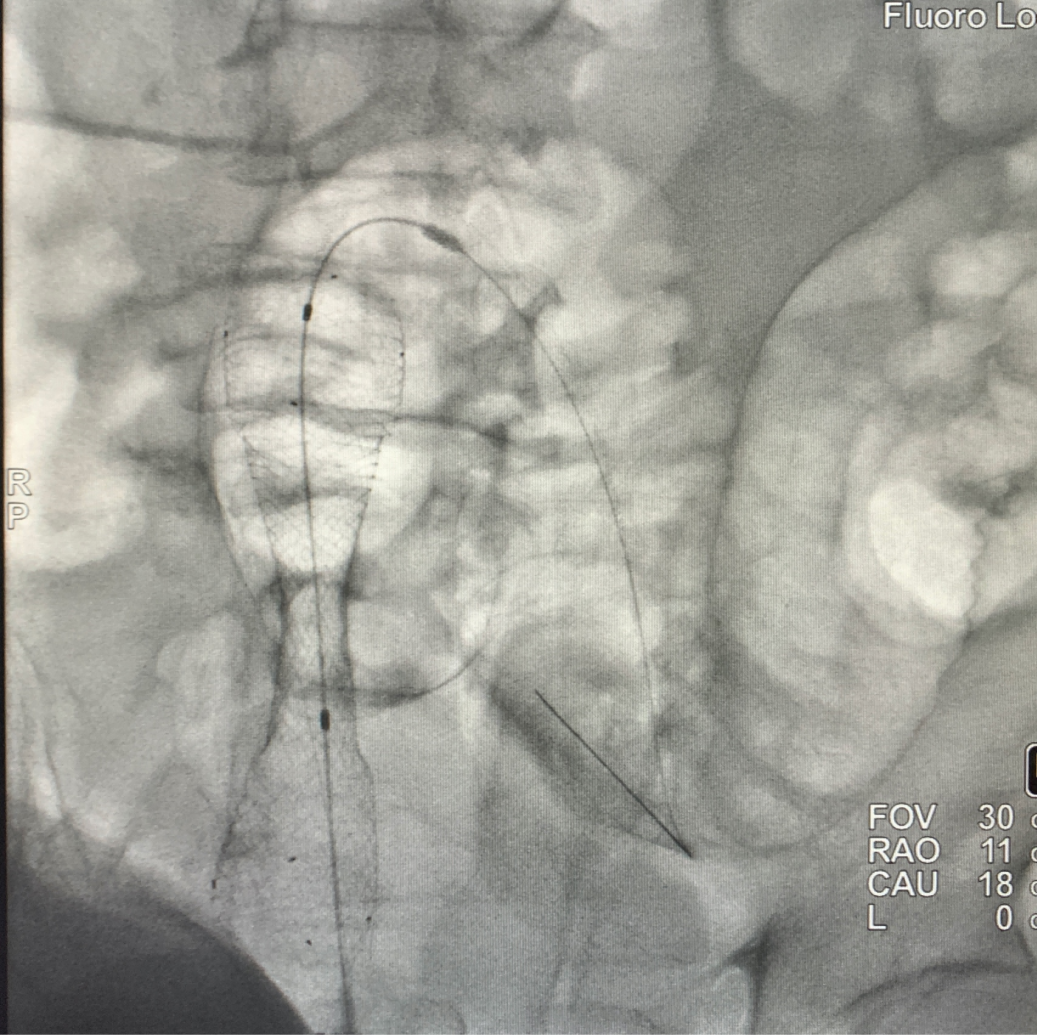

DSA 下造影剂无法通过,提示梗阻

通过导丝成功于直乙交界处放置支架

左图为放置支架前梗阻图像

右图为放置支架后第 2 天

梗阻解除